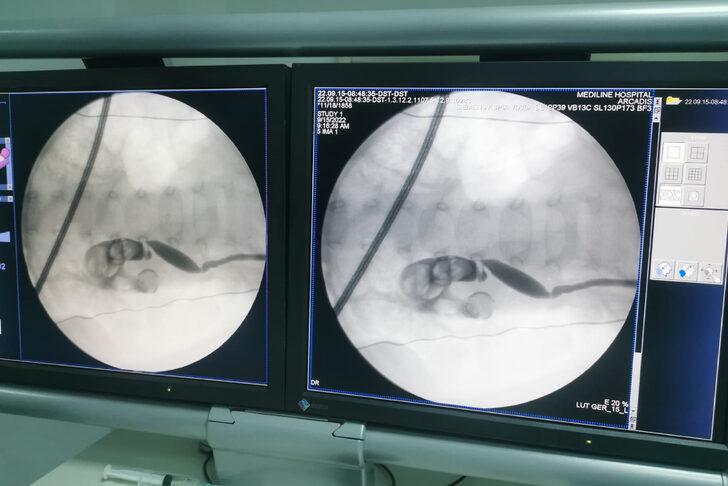

ELAZIĞ (AA) - Elazığ'da 13 aylık bebeğin böbreğindeki 5 santimetrelik taş, kapalı ameliyatla çıkarıldı.

Tetkiklerde bebeğin sol böbreğini kaplayan 5 santimetre büyüklüğünde taş olduğu tespit edildi.

Üroloji Uzmanı Serhat Yentür tarafından gerçekleştirilen kapalı ameliyatla bebeğin böbreğindeki taş kırılarak çıkarıldı.

Kapalı yöntemle böbrekteki taşı kırarak büyük bölümünü çıkardıklarını aktaran Yentür, "Tamamen temizlemek imkansız çünkü böbreğin içi oda oda yani bir boşluk şeklinde değil. Çocuğa zarar veren yüzde 99'a yakını temizlendi. Kalan taşlar da ekstra daha basit tedavi yöntemleriyle temizlenecek." diye konuştu.